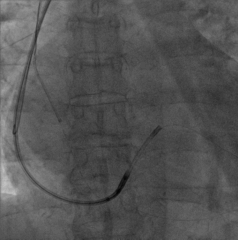

手术经过:首先冠脉造影延迟显影可见冠状窦开口及靶静脉大致走行

AP

LAO45

6225i球囊造影可见轻微夹层,远端未显影

6250VIS鞘管直接造影可见分支显示良好

LAO